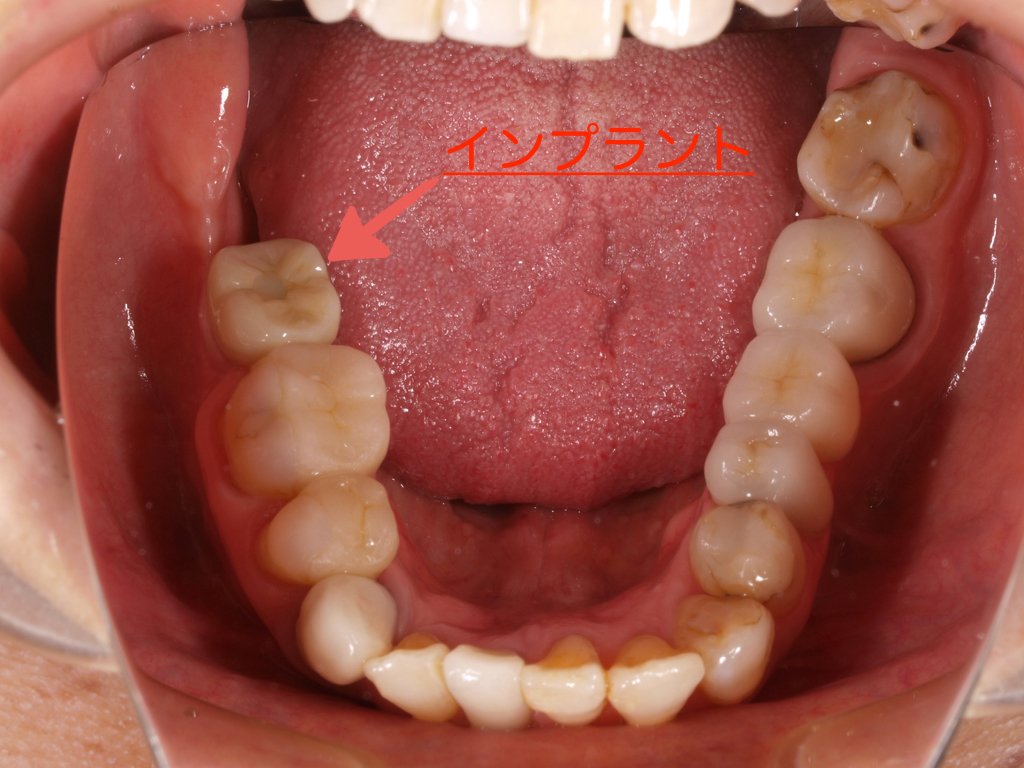

患者様は60代の女性で右下7番の歯が歯根破折で抜歯になり、抜歯後の欠損部にインプラント治療を行った症例です。

治療の流れとしては、静脈内麻酔下にて右下7番の欠損部の骨内に1本のスウェーデン製のノーベルバイオケア社のインプラント(フィクスチャー)を埋入して、ON1ベースアバットメント(土台)を装着して仮歯を経て最終上部構造(ジルコニアセラミック)をスクリュー固定しました。